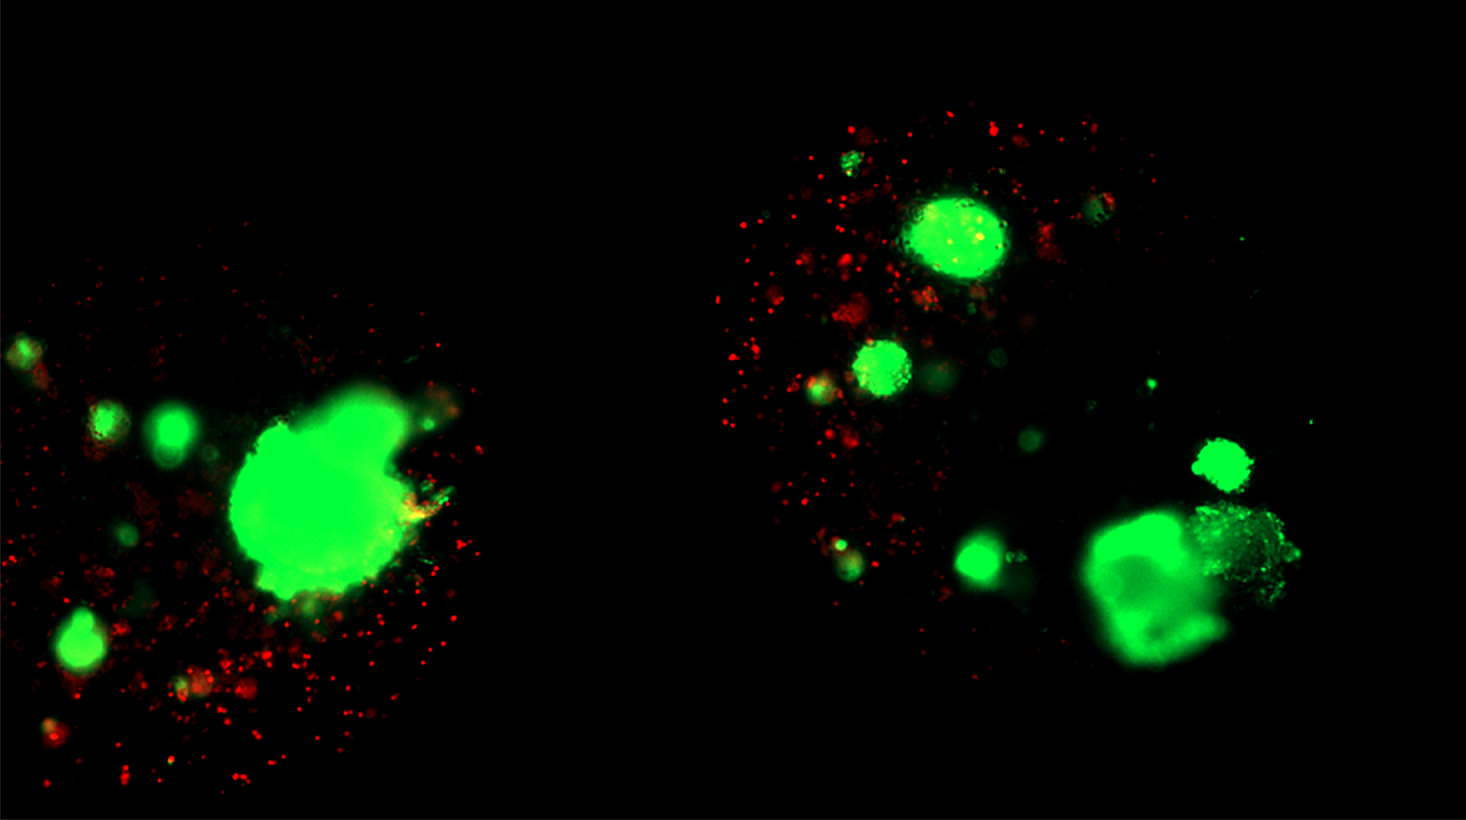

Encapsulated islets retained high viability and cellular integrity compared to standard (unencapsulated) cryopreservation, as confirmed by live/dead imaging.